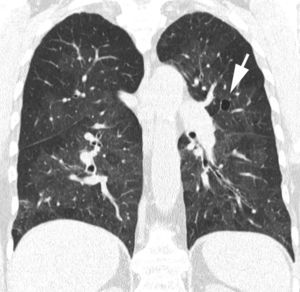

En la TCAR, la fase aguda de la AAE se caracteriza por la presencia de un patrón pulmonar difuso en «vidrio deslustrado», un patrón nodulillar o un patrón mixto, asociado muchas veces a áreas parcheadas de atrapamiento aéreo. En las fases crónicas, la presencia de un patrón reticular con desestructuración y retracción de los ejes broncovasculares refleja la presencia de fibrosis. Es frecuente el hallazgo asociado de áreas focales de atrapamiento aéreo (fig. 12)51.

Imagen TCAR centrada en lóbulos superiores en un paciente con alveolitis alérgica extrínseca en fase crónica, que destaca la presencia de opacidades reticulares, bronquiectasias de tracción y «vidrio deslustrado» (flechas), asociado a áreas focales de atrapamiento aéreo en lóbulo superior izquierdo (cabezas de flecha).